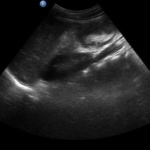

La invaginación intestinal es la causa más común de obstrucción intestinal en niños de 3 meses a 3 años. Se caracteriza porque un segmento de intestino penetra en otro segmento intestinal. Puede presentarse en colon, intestino delgado o entre intestino delgado y el colon. El resultado es la obstrucción intestinal.